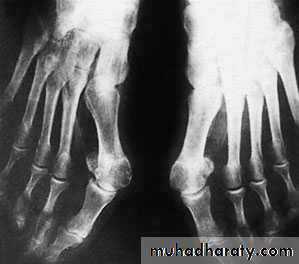

Hallux valgus:

It’s the commonest foot and musculoskletal deformity seen in practice.There is valgus deviation of the big toe with mild medial rotation where the nail facing slightly to the medial side, there is also overcrowding of the other toes with the 2nd. Toe usually develops the deformity known as hammer toe (extension of the metatarsophalangial joint, flexion of the proximal interphalangial and extension of the distal interphalangial joint).

The lst. metatarsal head looks thick and widened, and because of rubbing with shoe wear on its medial side there will be the formation of thick bony exostosis and over it there is a protective synovial bursa (the bunion) that may get swollen, inflamed or infected.

X-ray:

Taken with the patient standing to show the degree of metatarsal and hallux angulations.Also it shows the state of the joint being normal, arthritic or subluxated.